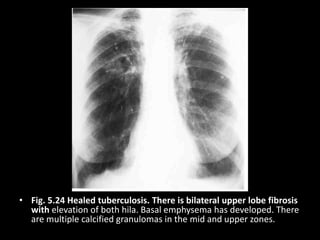

• Fig. 5.24 Healed tuberculosis. There is bilateral upper lobe fibrosis

with elevation of both hila. Basal emphysema has developed. There

are multiple calcified granulomas in the mid and upper zones.

• Fig. 5.24Healed tuberculosis. There is bilateral upper lobe fibrosis with elevation of both hila. Basal emphysema has developed. There are multiple calcified granulomas in the mid and upper zones.